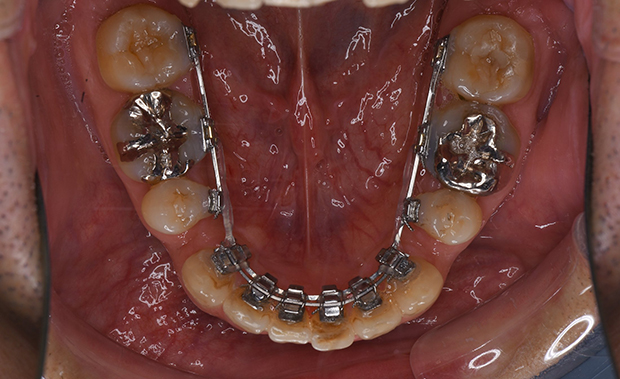

【フルリンガル】ガタガタ 抜歯 舌側マルチブラケット装置

| 主訴 |

ガタガタ |

||

|---|---|---|---|

| 診断名 |

右側Angle II級叢生 |

||

| 年齢 | 36歳 | 性別 | 男性 |

| 治療に用 いた装置 |

舌側マルチブラケット装置(セミカスタム) | 抜歯部位 | 上顎両側第一小臼歯 下顎両側第二小臼歯 |

| 治療期間 ・回数 |

2年6か月・30回 | 治療費 概算 |

約90万円 (調整料を含む) |

| 治療内容 詳細 |

舌側のマルチブラケット装置で治療した典型的な抜歯症例です。抜歯したスペースを利用して歯グキが下がらないよう安全面に配慮し歯を排列しました。 |

||

| リスク・ 副作用 |

装置による違和感、疼痛、歯根吸収など |

||